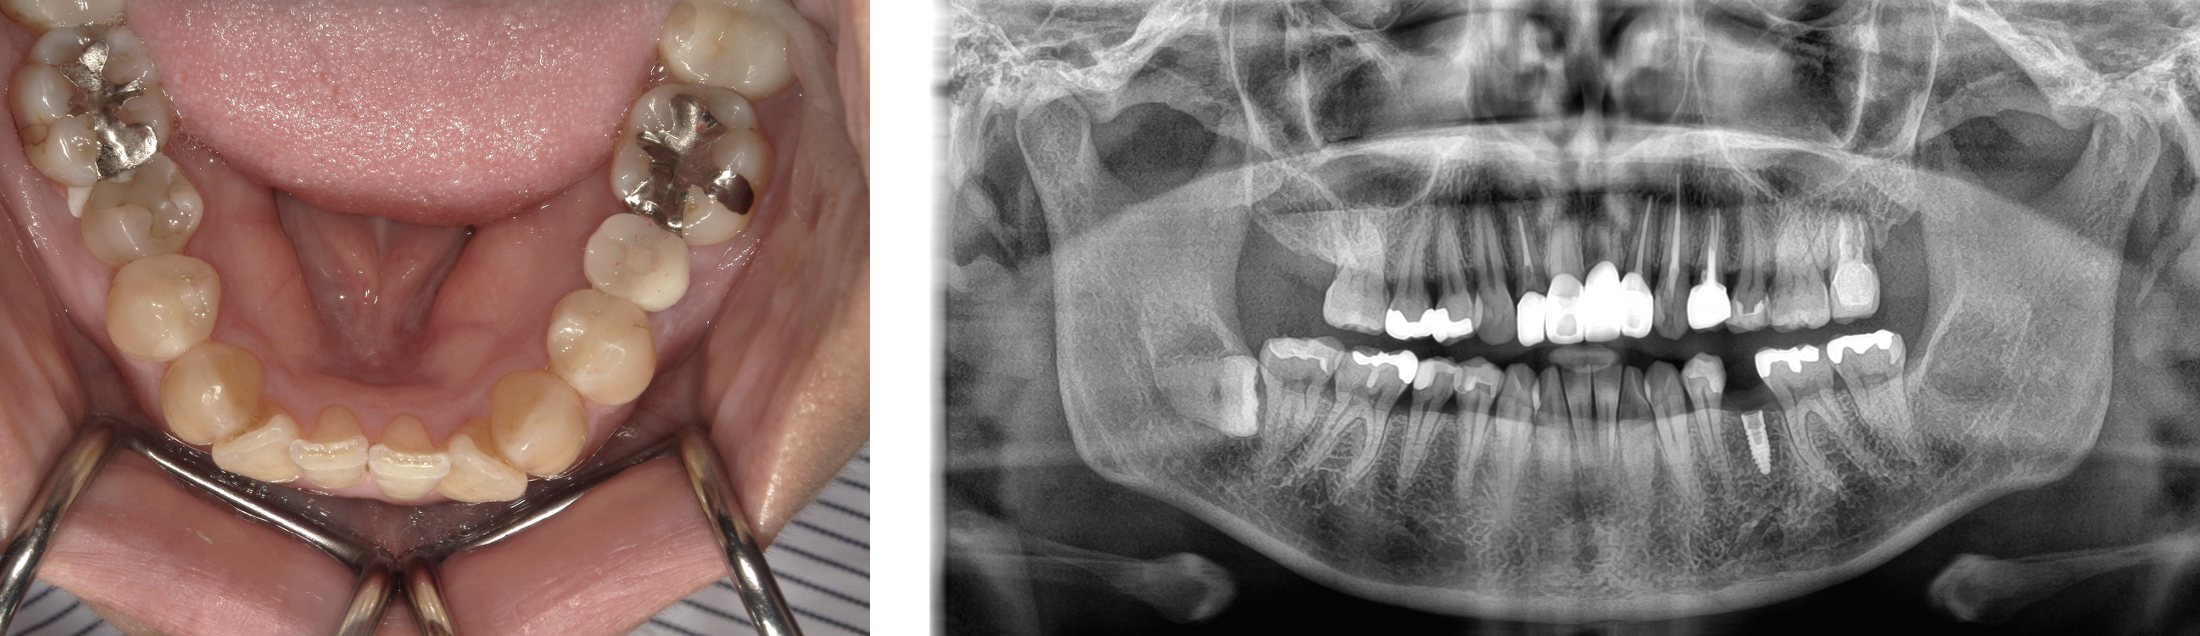

インプラント 症例2

左下5番にインプラントを行った症例

入れ歯からインプラントに変更